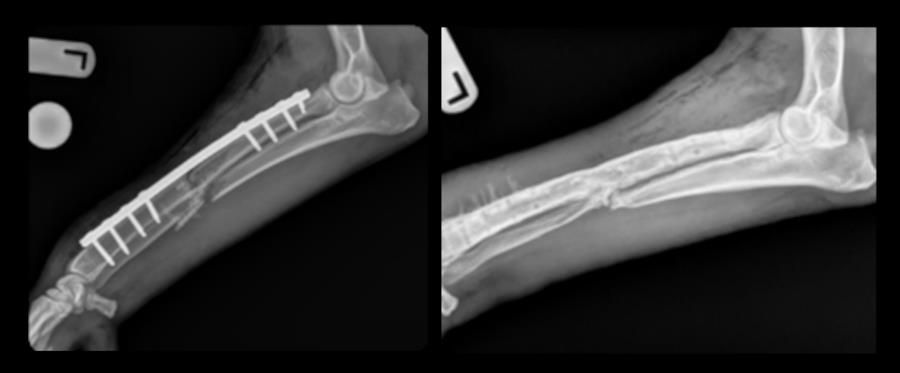

橈尺骨骨幹中段/開放性(Grade II)/粉碎性骨折

4 歲已絕育公德國狼犬,40 kg(肥胖)。車禍後出現左前肢嚴重橈尺骨骨折。此案同時存在就診延遲、開放性傷口(Grade II)、高度粉碎,以及肥胖造成的行動限制等多重挑戰。

主刀:Dr. Daniel Mertens, ACVS,採內固定處置:

3.5 mm 寬型動力加壓骨板(broad DCP,以 buttress 支撐模式)

ARCIS® 骨固定螺釘 fasteners(UnifiMI)

取自肱骨近端之自體皮質-鬆質骨移植(corticocancellous graft)

骨折區兩側各以 4 枚固定螺釘建立穩定跨越固定

如預期復原期較長;術後第 8、12、16 週 輪照均顯示骨癒合持續進展。術後 14 個月 因排膿性瘻管回診,X 光顯示骨折已完全癒合。隨後進行骨板移除,臨床症狀完全消失,恢復良好。